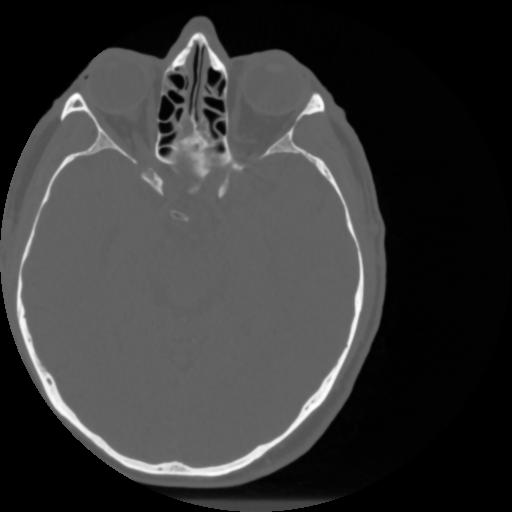

4 CEREBRO,,Vol,0.5,CEREBRO,,